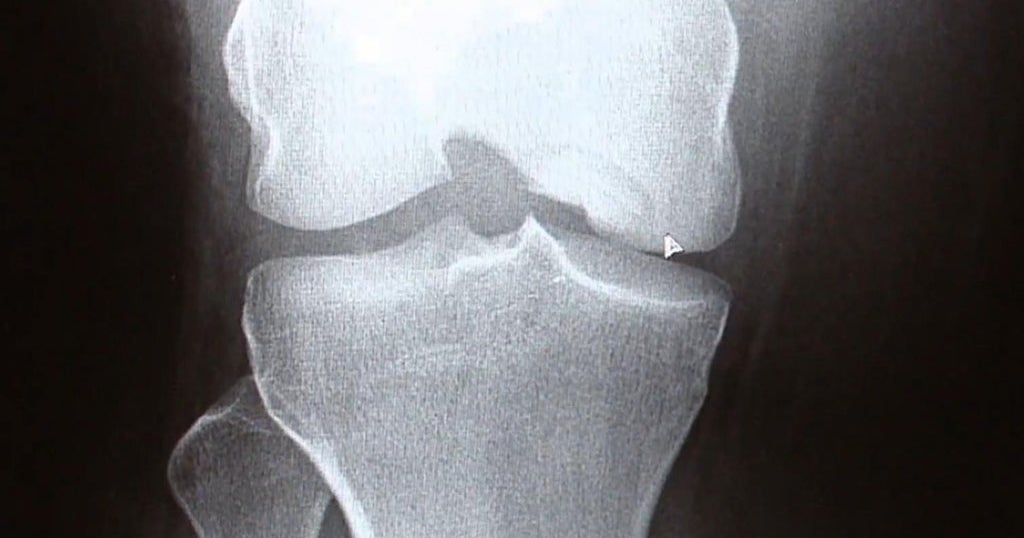

Knee XRay Price, Purpose, Results & Risks [2024] • Bookmerilab Noisy Joints Knees To help you better understand what you may be hearing, feeling, and seeing, here is a breakdown of the 9 most common causes of crackling, popping, snapping, creaking,. It concluded that grating, cracking, or popping sounds in or around the knee joints (a condition known as crepitus) may put some. When your knee creaks, pops, or cracks, is it a. Noisy Joints Knees.